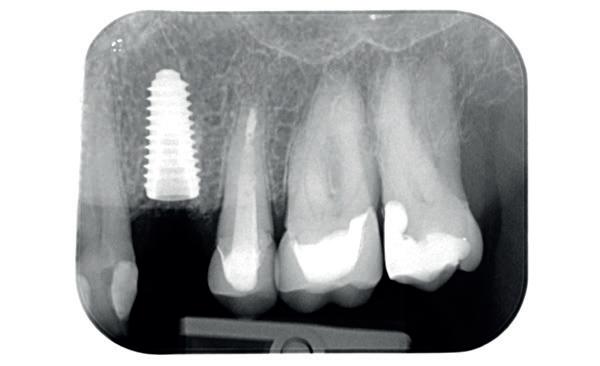

Tweede fase chirurgie

Na de genezingsperiode werd eerst een OPT röntgenopname vervaardigd om de genezing van de implantaten, kaakverbreding en sinusbodemelevatie te beoordelen. Er waren geen complicaties opgetreden. Bij de tweede fase chirurgie is het van absoluut belang dat er minimaal 2-3 mm gekeratiniseerd weefsel aan de buccale zijde van de implantaten wordt verkregen, anders kan de patiënt de implantaten niet goed reinigen en door de trekkrachten van de mucosa ontstaat al gauw peri-implantaire ontstekingen en recessies. De incisie hoeft niet van tuber tot tuber te zijn, maar 2 incisies van de 16 tot de 12 en 26 tot de 22 is voldoende, waarbij de incisie genoeg gekeratiniseerd weefsel aan de buccale zijde bevat, dat naar

de buccale zijde van de implantaten wordt geduwd. Er werden 6 healing abutments van 6 mm hoogte op de implantaten geplaatst, waarna de wonden werden gehecht met een 6-0 monofilament hechtdraad. In de prothese werd een nieuwe softliner over de healing abutments geplaatst. Het weefsel dient minimaal 4 weken genezingstijd te hebben (afbeelding 6).

De technicus leverde op basis van de tijdelijke brug, de vast brug op implantaten af. Deze is van volledig zirkoonoxide met een titanium frame aan de binnenzijde voor de stevigheid (afbeelding 16-18). Een volledige brug van alléén zirkoonoxide is namelijk fractuur gevoelig. Na verwijderen van de tijdelijke brug kon de mondhygiëne van de patiënt gecontroleerd worden bij de implantaten. Patiënt hield het netjes schoon met een elektrische tandenborstel en een waterpik. Het is van belang dat de brug zonder spanning op zijn plek geduwd kan worden en deze niet kan kantelen op de abutments. Na het plaatsen van de brug werden de schroefjes getorqued op 15 Ncm, waarna de esthetiek, occlusie en articulatie gecontroleerd konden worden.

Daarna werden de schroefgaten gevuld met Blue M gel, teflon tape en composiet (afbeelding 19 en 20). Patiënt was zich zeer tevreden met het functionele en esthetische eindresultaat (afbeelding 19 en 20). Er was ook een nette hoektand en frontgeleiding. Voor de fonetiek werd een filmpje opgenomen, de F en de S werden netjes uitgesproken (afbeelding 21). De patiënt vervolgt zijn parodontale nazorg bij de mond-

hygiënist waarbij ook de mondhygiëne bij de brug wordt gecontroleerd. Op de OPT na 2 jaar (afbeelding 22) is het botniveau rondom de implantaten stabiel en is patiënt tevreden met zijn vaste brug.

22. Controle OPT na 2 jaar